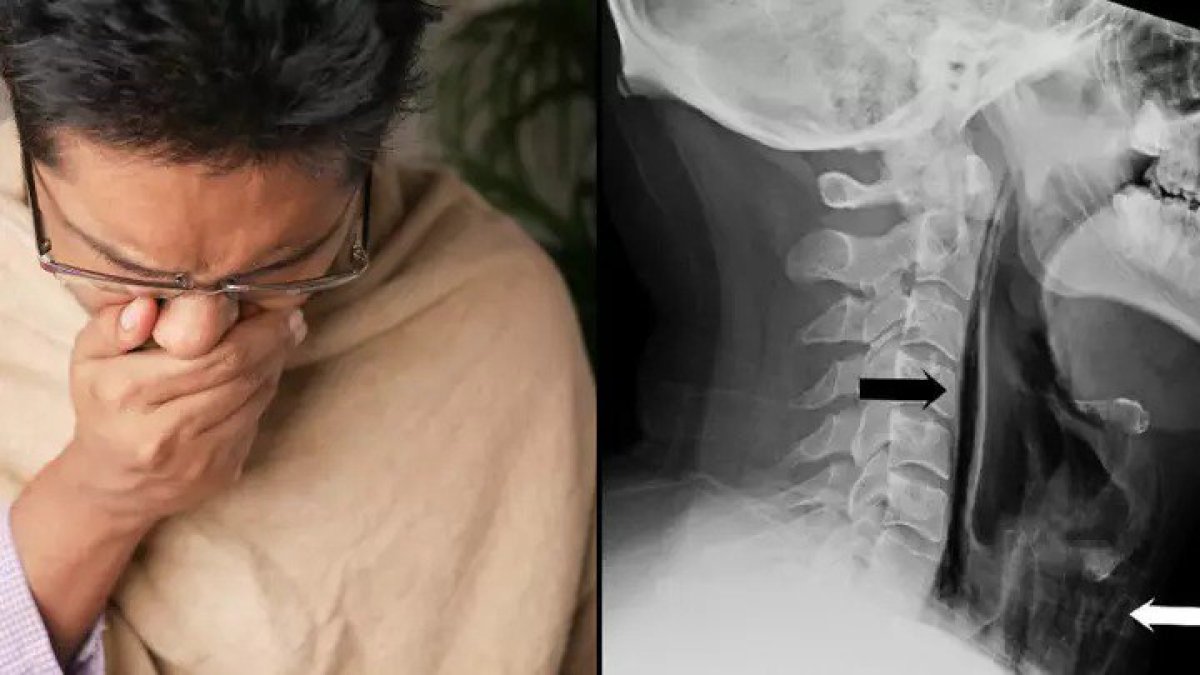

Мужчина сдержал чих и попал в больницу с травмой горла

Неприятный случай произошел с британцем. Он буквально надорвал горло, пишет Astana TV по материалам KP.ru

Пациент поступил в больницу с жалобами на острую боль при глотании и на изменения в голосе после сильного чиха. Он рассказал врачам, что попытался сдержать позыв чихнуть, зажав ноздри пальцами, но когда чихнул, то почувствовал толчки в шее и затем обнаружил, что шея опухла.

Рентгеновский снимок показал, что в глотку мужчины попал воздух, и давление вызвало повреждение. Врачи заявили, что британец в прямом смысле надорвал своё горло. К счастью, травма была не серьёзной, и операция не потребовалась.